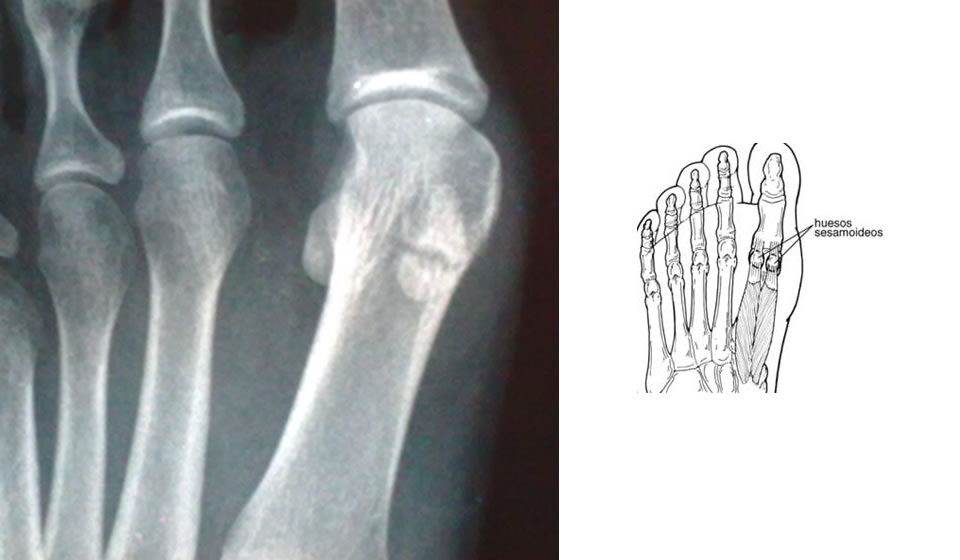

El Hallux presenta dos huesos sesamoideos constantes a nivel de la articulación Metatarsofalángica     y un hueso sesamoideo inconstante en la articulación Interfalángica.

Los Sesamoideos metatarsofalángicos ( MTF ) son denominados Medial ( Tibial o Interno ) y Lateral ( Fibular, Peróneo o Externo).  Se forman de múltiples centros de osificación, que finaliza entre los 7 y 10 años de edad.  Para la mayoría de los au tores  la falta de dicha unión explicaría la existencia de Sesamoideos Bi, Tri, o Multipartitos. Son de forma ovoidea. El Sesamoideo Interno mide aproximadamente 12 - 15 mm por 9 - 11 mm y el Externo 9 - 10 mm por 7 - 9 mm.  Se encuentran incluidos en el espesor del tendón del flexor corto del Hallux y ubicados a ambos  lados de la cresta intersesamoidea en el aspecto plantar de la cabeza del primer metatarsiano; con la cual contactan por su superficie articular recubierta de cartílago presentando tejido y líquido sinovial.

Además el Sesamoideo interno recibe inserciones del fascículo interno del flexor corto y del abeductor del hallux, y está unido a la cápsula interna articular. El Sesamoideo externo recibe inserciones del fascículo externo del flexor corto y de los fascículos oblicuo y transverso del aductor que corren sobre el ligamento metatarsiano transverso.  Estos tendones van del sesamoideo externo a la cara plantar externa de la base de la primera falange, este sesamoideo se une al cuello del segundo metatarsiano por la porción profunda del ligamento intermetatarsiano, ( si se secciona éste, el sesamoideo se reduce con facilidad ). Por encima del ligamento intersesamoideo transcurre el tendón del flexor largo del  hallux al cual  protegen antes de su inserción en la falange distal. En ocasiones existe una bursa entre el sesamoideo interno y la piel, ambos sesamoideos están separados de ésta por la almohadilla plantar.